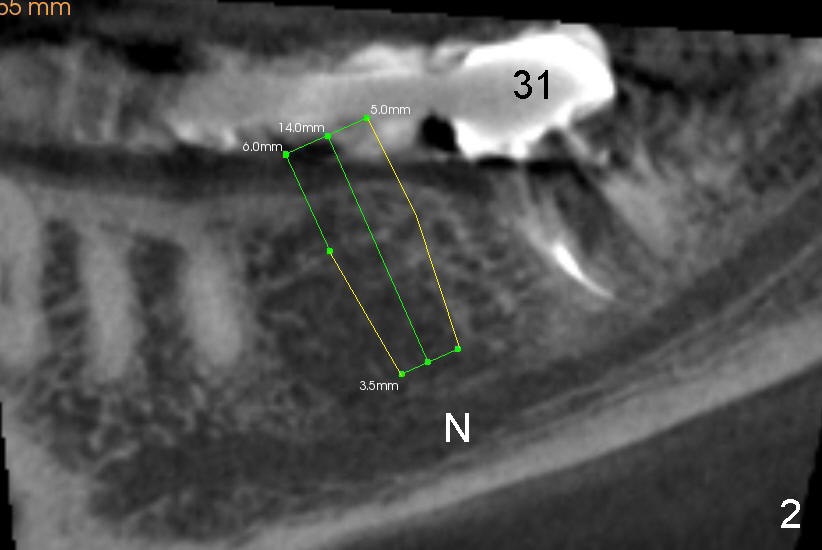

A Caucasian lady has a failing bridge in the lower right quadrant. After sectioning the bridge, the tooth #31 is extracted and an immediate implant is placed (7X11 mm). A 5x14 mm tapered implant is planned to be placed at the site of #30 six weeks later (Fig.1,2). Since the top of the ridge is severely atrophic and the mesiodistal width is quite wide, I wonder whether we should place a D2 or 3 short implant instead. My concern is how to create a D shaped osteotomy without offset D osteotomes, although bone scalpel and bone blade osteotomes can be used to create an initial osteotomy. Thanks.